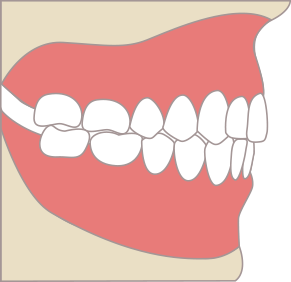

八重歯:犬歯が外に出ている場合

犬歯という歯が唇側に大きく出ていると、犬歯がかみ合いません。

歯は種類ごとに、機能があるため、犬歯がかみ合っていないということは、犬歯が機能していないということになります。

犬歯は、前歯と奥歯と違った大事な機能があります。犬歯は顎を横にスライドするときに機能します。ご飯を食べるとき、人は厳密にはカチカチ噛んでいるわけでなく、顎をスライドして咀嚼します。そのため、咀嚼する時には、横にずれる動きが存在しています。

犬歯が噛んでいないと、横の動きを他の歯で代償することになります。主に横の動きを代償する歯は、臼歯になります。臼歯は頑丈そうに見えて横の力に弱く、犬歯が噛んでいないと、経年的に奥歯が悪くなります。

奥歯を横の力から守るために、犬歯を矯正治療で移動させ、しっかりと機能させてあげることが必要です。

八重歯と(叢生)と奥歯への負担

正常な咬み合わせ(犬歯誘導)

犬歯がガイドし、奥歯が離れる

八重歯の場合(奥歯の干渉)

犬歯が機能せず、

奥歯が強く当たる(過度な負担)

破折・歯周病の

リスク